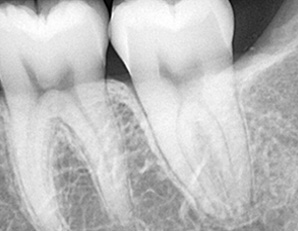

하나치근단 촬영을 통한 정확한 진단 -